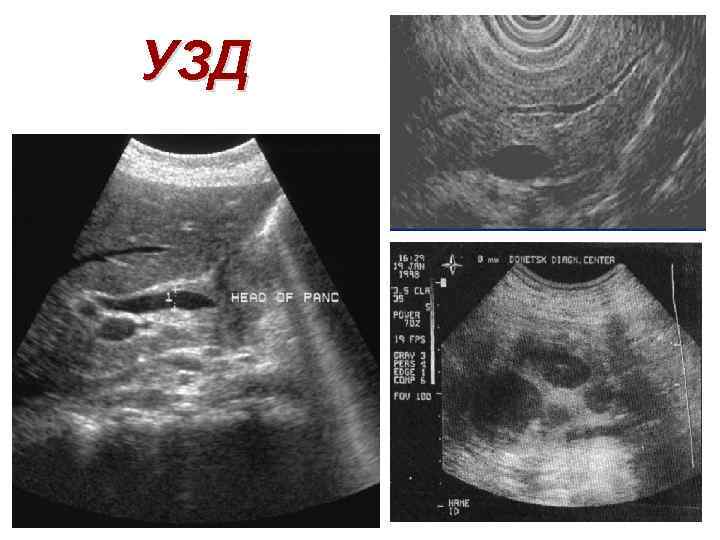

УЗД

УЗД